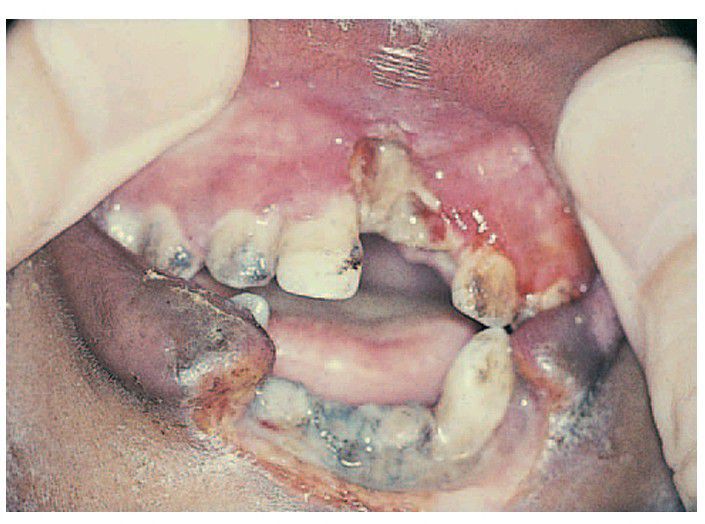

Cancrum oris.

In the maxilla there is extension of necrotising gingivitis into the alveolar process and in the lower arch anteriorly, resulting in destruction of much of the lower lip.